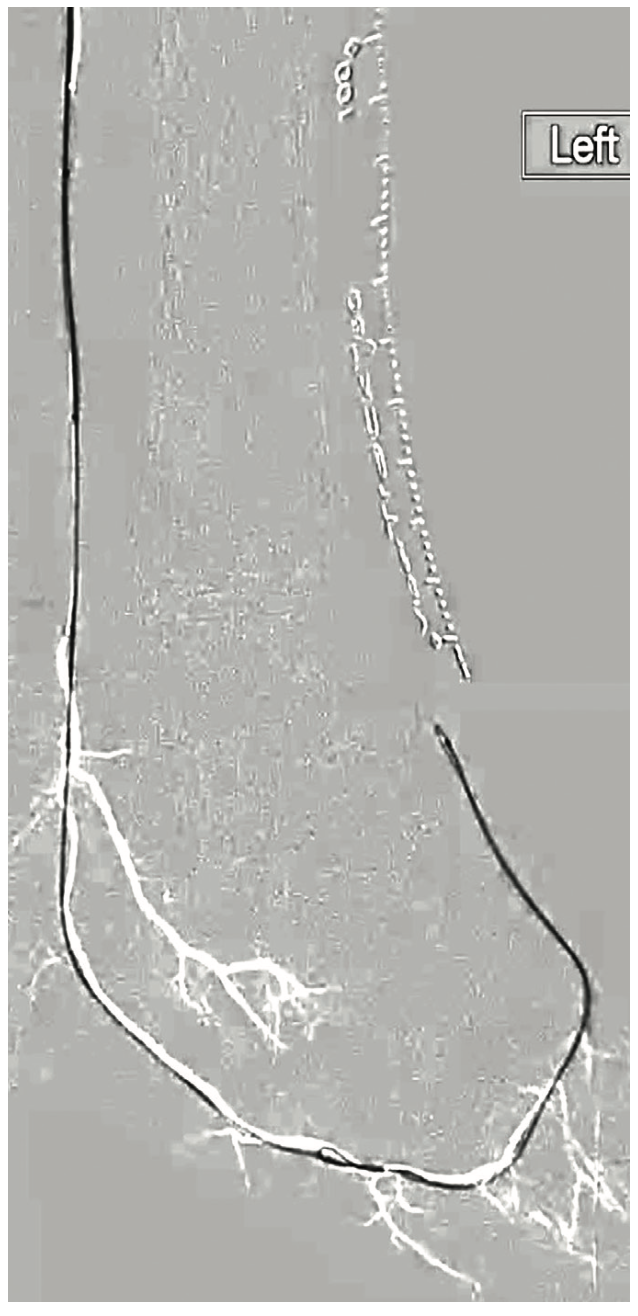

In cases where the tibial vessels do not reconstitute above the ankle, we choose to perform a modified Schmidt access of the occluded vessel. This is a technique where the operator accesses the occluded portion of the vessel using ultrasound guidance. Access into the distal occluded PT was performed using a V-18 wire. An antegrade access with a 5 French sheath was utilized to advance an .035-inch Navicross catheter (Terumo) to engage the proximally occluded PT using an Astato .014-inch 20-gram tip wire (Figure 3). Using the tunneling technique, we were able to advance the retrograde V-18 wire into the antegrade Navicross catheter (Figure 4). We chose to floss a Viper wire between the antegrade sheath and the pedal access. After plaque modification in the PT followed by balloon angioplasty, an .014-inch catheter was advanced inside the Navicross over the flossed Viper wire (from the CFA to the PT access point). At this stage, the Viper wire was removed and a Regalia .014-inch wire was advanced into the plantar circulation (Figure 5).

Interestingly, the DP across the ankle joint had what appeared to be a “White Stop Sign”. We have provided an image of the DP under ultrasound and fluoroscopy (Figure 6). The White Stop Sign is a term we use to describe a vessel that is completely opacified with calcified plaque and occupies a long segment of the vessel, making it difficult to cross. In this case, we were able to achieve partial pedal loop reconstruction. This ultimately allowed blood flow to the inferior digital branch, achieving adequate angiosome revascularization (Figures 7-8).